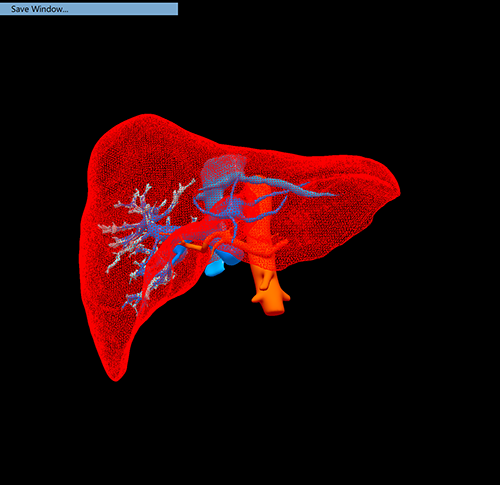

右肝癌---右三肝切除

介入后2周